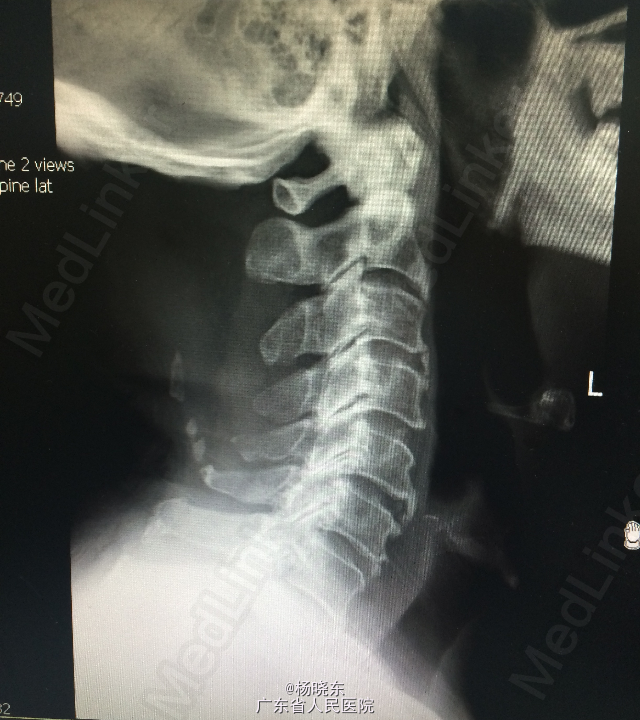

查体:贫血貌,心肺腹查体无特殊。 辅查: 1.全长双下肢长骨正位+尾椎正侧位+肋骨正位+右关节正位+骨盆正位+腰椎正侧位+下胸椎正侧位放射常规照片示:考虑多发性骨髓瘤(多发骨病变)。1、颈椎退行性变 2、腰椎退行性变;多个椎间盘病变;L1椎体轻度压缩性骨折。3、胸椎退行性变。 2.骨髓活检:可见少许造血成分,粒红比例大致正常,均以中晚幼阶段细胞为主,全片可见三个巨核细胞,形态未见明显异常。并可见浆细胞散在。 3.骨髓-外周血涂片:MM-骨髓增生活跃,浆细胞占58.0%,其中原幼浆占53.5%,外周血占2.0%。